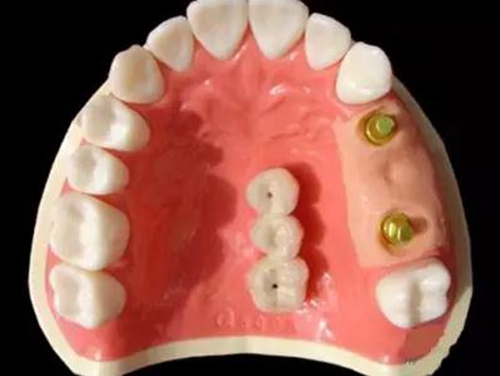

種植支持式固定義齒外展隙面積影響食物嵌塞

8月13日在線發(fā)表于《牙周病學雜志》(J Periodont)的一項橫斷面研究顯示,種植支持式固定義齒和鄰牙間的食物嵌塞更易發(fā)生于鄰接觸喪失及外展隙表面積(ESA)增加的情況下。食物嵌塞降低了患者的總體滿意度。外展隙尺寸影響牙周/種植體周黏膜的狀態(tài)及種植體的骨水平。

本研究納入了100例患者(55 例男性,45 例女性),平均年齡56歲(27~83歲),共150個固定義齒的215個外展隙。牙周/種植體周圍黏膜狀態(tài)、外展隙尺寸及患者總體滿意度作為解釋變量。

結(jié)果在種植支持式固定義齒和鄰牙間的215個外展隙中,96個(44.7%)有食物嵌塞。鄰接觸喪失外展隙較緊密接觸者更易發(fā)生食物嵌塞(P=0.009)。鄰面外展隙的食物嵌塞降低了總體滿意度(P=0.012)。在外展隙參數(shù)中,僅ESA明顯影響食物嵌塞(P=0.034)。不同的外展隙尺寸對牙周/種植體周黏膜狀態(tài)和種植體骨水平有顯著影響。

5.jpg